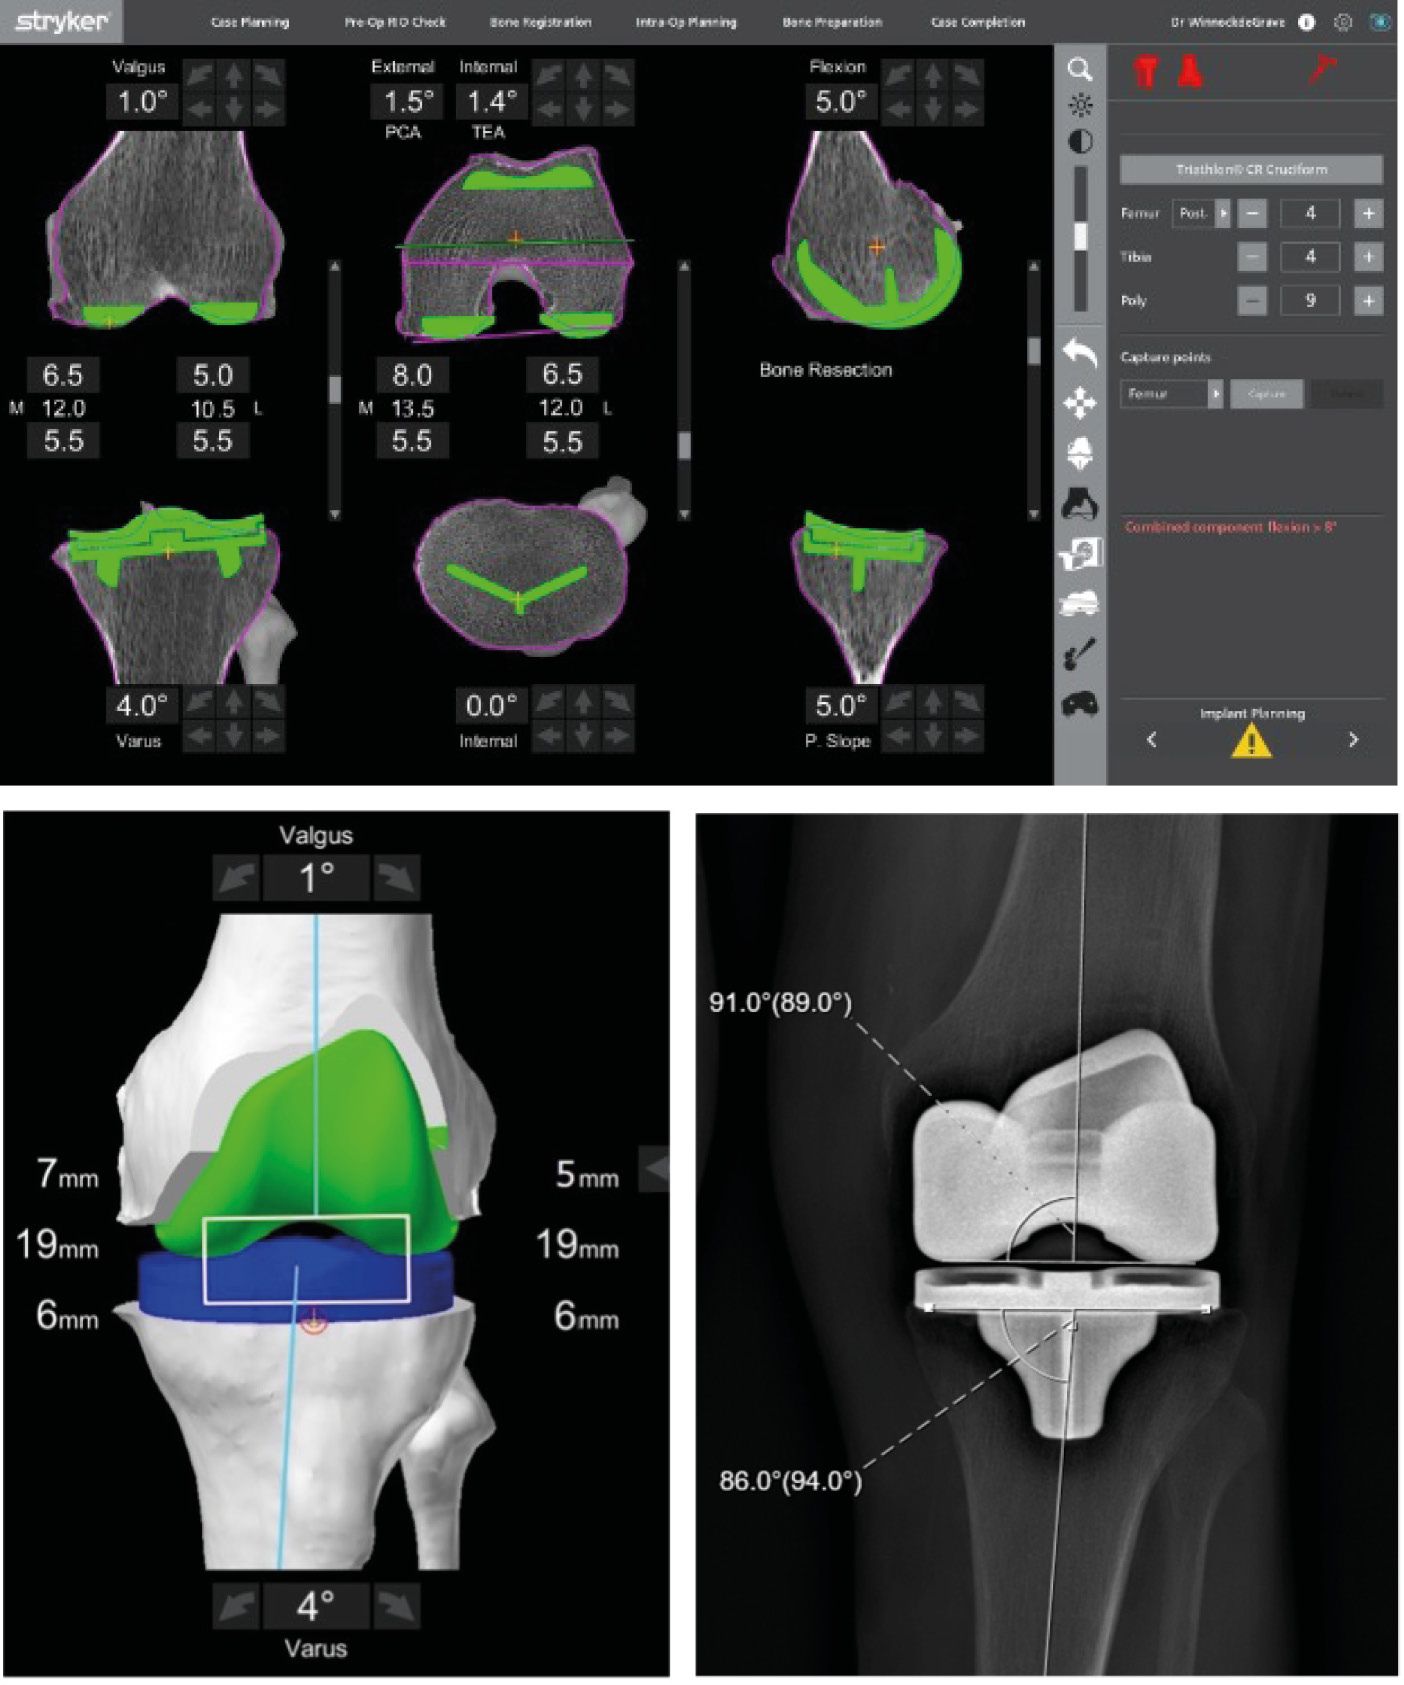

More recently, Winnock de Grave introduced the inverse kinematic alignment (iKA) as new patient specific alignment concept [39] Winnock de Grave, P., Luyckx, T., Claeys, K. et al. Higher satisfaction after total knee arthroplasty using restricted inverse kinematic alignment compared to adjusted mechanical alignment. Knee Surg Sports Traumatol Arthrosc 30, 488–499 (2022). https://doi.org/10.1007/s00167-020-06165-4. iKA favors the restoration of tibial joint line obliquity as first step (Figure 1). This is followed by resection of the posterior and distal femur bone by using the gap balancing technique to achieve ligament balance without releasing soft tissues. By resecting equal amounts of bone on the medial and lateral tibial condyle the native tibial joint line obliquity is restored (Figures 2, 3, 4). In iKA also boundaries are set to attenuate extreme morphotypes. When the target zones of iKA, rKA and MA are compared, the iKA target zones matches a higher proportion of native knee alignment, followed by rKA and MA [40] Winnock de Grave, P., Luyckx, T., Van Criekinge, T. et al. Inverse kinematic alignment accommodates native coronal knee alignment better in comparison to adjusted mechanical alignment and restricted kinematic alignment. Knee Surg Sports Traumatol Arthrosc (2023). https://doi.org/10.1007/s00167-023-07326-x. Analysis of the tibial position in iKA in the coronal plane shows a mean postoperative MPTA of 86,5°, corresponding to the native joint line obliquity [40] Winnock de Grave, P., Luyckx, T., Van Criekinge, T. et al. Inverse kinematic alignment accommodates native coronal knee alignment better in comparison to adjusted mechanical alignment and restricted kinematic alignment. Knee Surg Sports Traumatol Arthrosc (2023). https://doi.org/10.1007/s00167-023-07326-x. The femoral position with the iKA shows a mean external rotation of 2° relative to the posterior condylar axis (PCA) and 2° varus position according to the native LDFA of 86° [8], Chao TW, Geraghty L, Dimitriou P, Talbot S. Averaging rotational landmarks during total knee arthroplasty reduces component malro- tation caused by femoral asymmetry. J Orthop Surg Res 2017;12:74, http://dx.doi.org/10.1186/s13018-017-0575-2 [PMID: 28499396; PMCID: PMC5429545]. [29], Ng CK, Chen JY, Yeh JZY, Ho JPY, Merican AM, Yeo SJ. Distal femoral rotation correlates with proximal tibial joint line obliquity: a considera- tion for kinematic total knee arthroplasty. J Arthroplasty 2018;33:1936–44, http://dx.doi.org/10.1016/j.arth.2017.12.025 [Epub 2017 Dec 28. PMID: 29395720]. [39] Winnock de Grave, P., Luyckx, T., Claeys, K. et al. Higher satisfaction after total knee arthroplasty using restricted inverse kinematic alignment compared to adjusted mechanical alignment. Knee Surg Sports Traumatol Arthrosc 30, 488–499 (2022). https://doi.org/10.1007/s00167-020-06165-4. Whereby, when using off the shelf implants, this varus orientation of the trochlear groove leads to an optimal patellofemoral tracking [36] V Vigdorchik JM, Wakelin EA, Koenig JA, Ponder CE, Plaskos C, DeClaire JH,Lawrence JM, Keggi JM, Impact of Component Alignment and Soft Tissue Release on 2 Year Outcomes in TKA, J Arthroplasty (2022), https://doi.org/10.1016/j.arth.2022.04.042.. A clinical study comparing iKA with MA at 12 months follow up shows that higher proportions of iKA knees are satisfied and higher proportion of iKA knees that reach the patient accepted symptom state (PASS) thresholds for the Oxford Knee Score (OKS) [39] Winnock de Grave, P., Luyckx, T., Claeys, K. et al. Higher satisfaction after total knee arthroplasty using restricted inverse kinematic alignment compared to adjusted mechanical alignment. Knee Surg Sports Traumatol Arthrosc 30, 488–499 (2022). https://doi.org/10.1007/s00167-020-06165-4.

1. In the coronal plane

With iKA, the aim is to restore the native joint line obliquity (JLO), by restoring the individual MPTA and to restore the native limb alignment (HKA axis). The native MPTA is restored by performing equal bony resections medial and lateral on the tibial plateau. The MPTA is restored within the boundaries of 84° (varus) and 92° (valgus) preventing extreme implant positions. These boundaries represent native tibial alignment in 93% of Caucasian knees. [40] Winnock de Grave, P., Luyckx, T., Van Criekinge, T. et al. Inverse kinematic alignment accommodates native coronal knee alignment better in comparison to adjusted mechanical alignment and restricted kinematic alignment. Knee Surg Sports Traumatol Arthrosc (2023). https://doi.org/10.1007/s00167-023-07326-x The postoperative coronal limb alignment (HKA) is restored within the boundaries of 6° varus and 3° valgus. Postoperative limb alignment up to 6° varus have shown no deleterious effect on implant survival in long term survival studies. [1], Abdel M, Ollivier M, Parratte S, Trousdale R, Berry D, Pagnano M. Effect of post-operative mechanical axis alignment on survival and functional outcomes of modern[19], Hungerford DS, Krackow KA.Total joint arthroplasty of the knee. Clin Orthop Relat Res. 1985; 192: 23-33https://doi.org/10.1097/00003086-198501000-00004[35] Vendittoli PA, Martinov S, Blakeney WG. Restricted kinematic alignment, the fundamentals, and clinical applications. Front Surg. 2021; 8: 697020. https://doi.org/10.3389/fsurg.2021.697020 On the femoral side, the femoral component is positioned using the gap balancing technique to gain a symmetric extension gap. Furthermore the femoral implant restores the native medial joint line height as good as possible which will result in MCL isometry and prevent mid-flexion instability [24] MacDessi SJ, Griffiths-Jones W, Harris IA, Bellemans J, Chen DB. The arithmetic HKA (aHKA) predicts the constitutional alignment of the arthritic knee compared to the normal contralateral knee, a matched-pairs. Bone Joint Open 2020;1-7:339–345. doi: 10.1302/2633-1462.17..

2. In the sagittal plane

The slope of the tibial resection is performed parallel to the native medial tibial slope, with a maximum of 8° posterior slope [11] Farooq H, Deckard ER, Carlson J, Ghattas N, Meneghini RM, Coronal and Sagittal Component Position in Contemporary TKA: Targeting Native Alignment Optimizes Clinical Outcomes, J Arthroplasty (2023), https://doi.org/10.1016/j.arth.2023.04.040.. The femoral flexion is set to match the native anatomy, yet it is a compromise between femoral posterior offset, respecting the posterior condyle and avoiding notching the anterior cortex. The adjustment of the femur component size and flexion between 0 and 8° enable us to optimize this positioning in the sagittal plane [42] Yoshinori O, Shuhei O, Mikio N, Tsuyoshi J, Hitoshi W, Masashi N. Sagittal Alignment of the Femoral Component and Patient Height Are Associated With Persisting Flexion Contracture After Primary Total Knee Arthroplasty. J Arthroplasty 34 (2019) 1476e1482.

3. In the axial plane

The rotation of the femoral component determines the balancing of the flexion gap by using the balanced gap technique. Concerning the medial compartment in flexion, the target is to restore the native joint line level. When the PCL is retained, a slight over resection of the posterior condyles is sometimes necessary to open up the flexion gap and enable the entrance of the minimal insert thickness. This is allowed in iKA, but not in KA. The medial compartment in flexion must be balanced, with a remaining laxity of 1 or 2mm. On the lateral side however, the native laxity is reproduced with a joint opening up to 4 mm according to the native patient’s laxity. Rotation of the tibial component is set to Akagi’s line [2] Akagi M, Oh M, Nonaka T, et al. An anteroposterior axis of the tibia for total knee arthroplasty. Clin Orthop. 2004:213–219. .